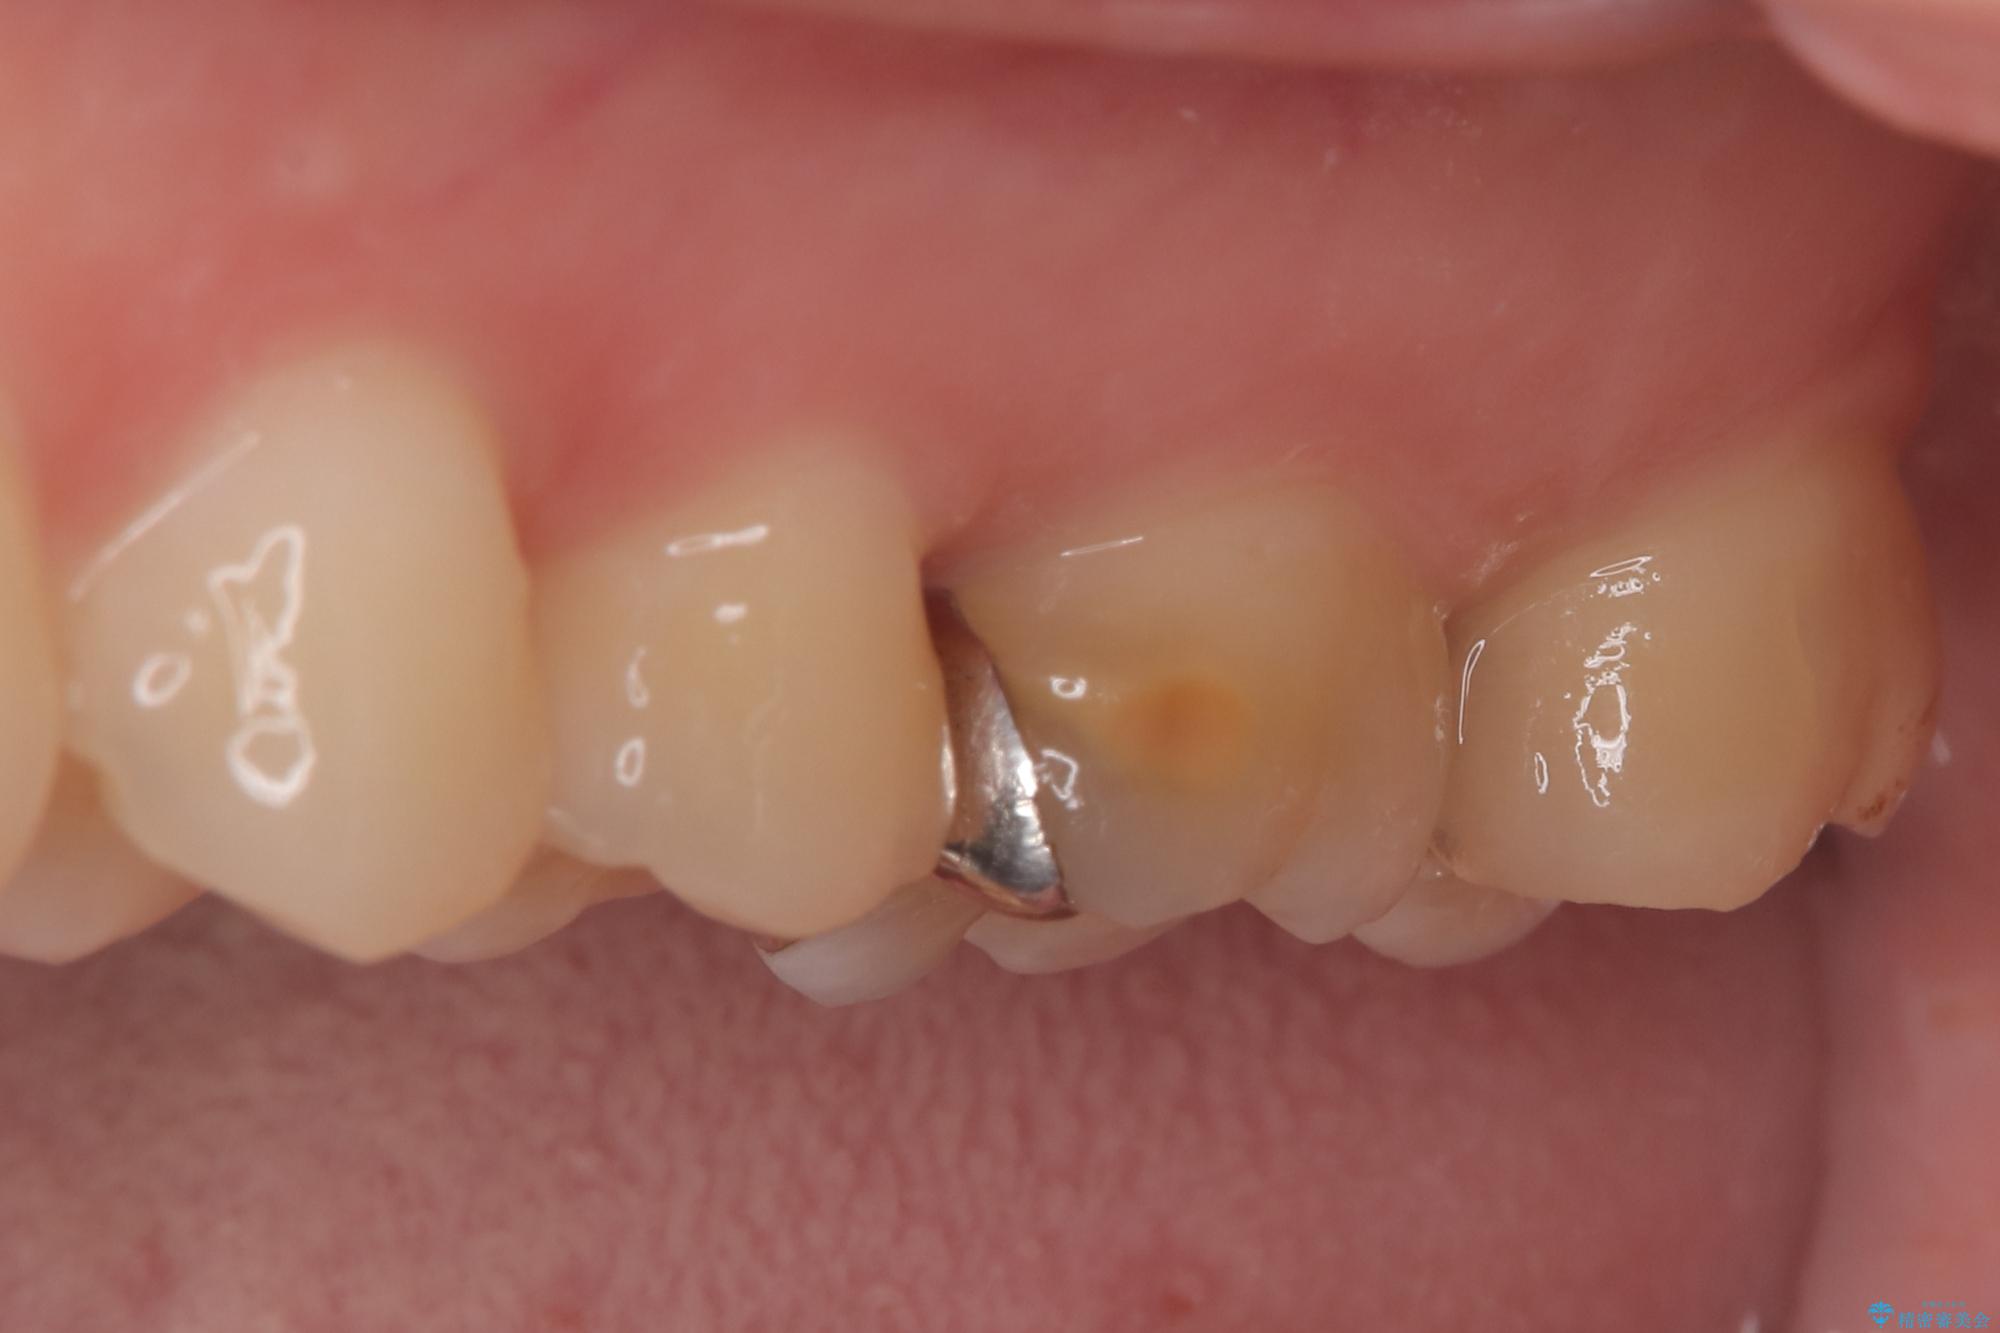

- 「冷たいものが強くしみる」という主訴でご来院されました。精密な診査の結果、虫歯が非常に深く、通常であれば神経を全て抜く「抜髄(ばつずい)」が必要な状態でした。しかし、神経を抜くと歯の寿命が縮まってしまうため、今回は神経の一部を温存する**「部分的断髄法(VPT)」**を提案しました。高い殺菌性と封鎖性、そして組織の再生を促す効果を持つMTAセメントを使用して神経を保護し、最終的には強度と審美性に優れたセラミックで修復する計画を立案しました。

部分的断髄法(MTAの使用): ラバーダム防湿を行い、無菌的な環境下で虫歯を慎重に除去。神経の露出を確認した後、炎症を起こしている一部の神経のみを除去し、残りの健全な神経を保護するためにMTAセメントを充填しました。これにより、神経の機能を維持し、歯を内部から守ることが可能となりました。